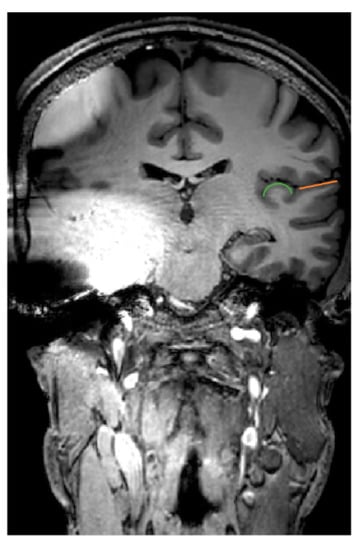

- Majdani, E.; Majdani, O.; Steffens, M.; Warnecke, A.; Lesinski-Schiedat, A.; Lenarz, T.; Götz, F. Dimensions of artefacts caused by cochlear and auditory brainstem implants in magnetic resonance imaging. Cochlear Implants Int. 2020, 21, 67–74. [Google Scholar] [CrossRef] [PubMed]

- Majdani, O.; Rau, T.S.; Götz, F.; Zimmerling, M.; Lenarz, M.; Lenarz, T.; Labadie, R.; Leinung, M. Artifacts caused by cochlear implants with non-removable magnets in 3T MRI: Phantom and cadaveric studies. Eur. Arch. Otorhinolaryngol. 2009, 266, 1885–1890. [Google Scholar] [CrossRef] [PubMed]